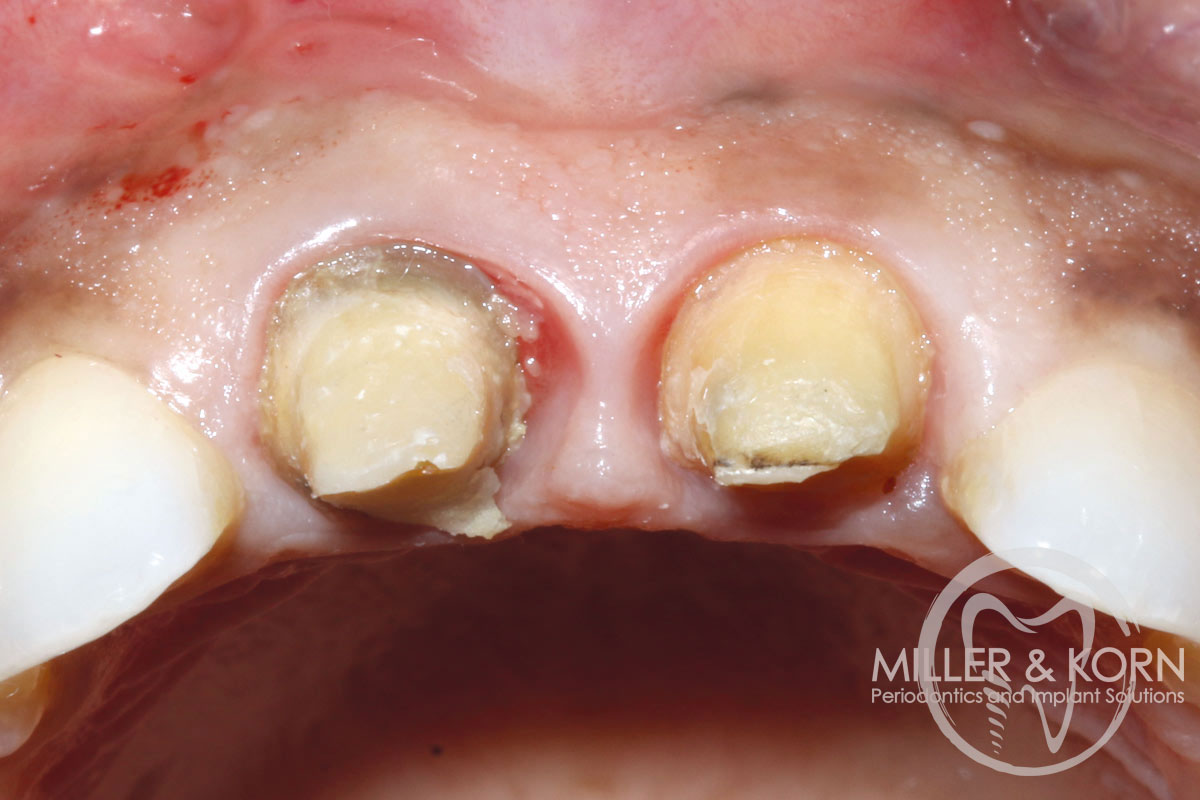

1/22 - 60-year-old female patient presented with a chronic infection on tooth #11. Since she has a high lip line matching the gingival margins of the adjacent central incisor and creating a root eminence is extremely important. For these reasons, the treatment of choice was an allograft bone ring enabling immediate placement of the dental implant with simultaneous regeneration of her ridge.Immediate implant placement and regeneration of ridge using an allograft bone ring and Jason® membrane - Drs. Miller and Korn

2/22 - She experienced trauma as a child and had fractured both tooth #8 and 9 which had been crown several times for esthetics.Immediate implant placement and regeneration of ridge using an allograft bone ring and Jason® membrane - Drs. Miller and Korn